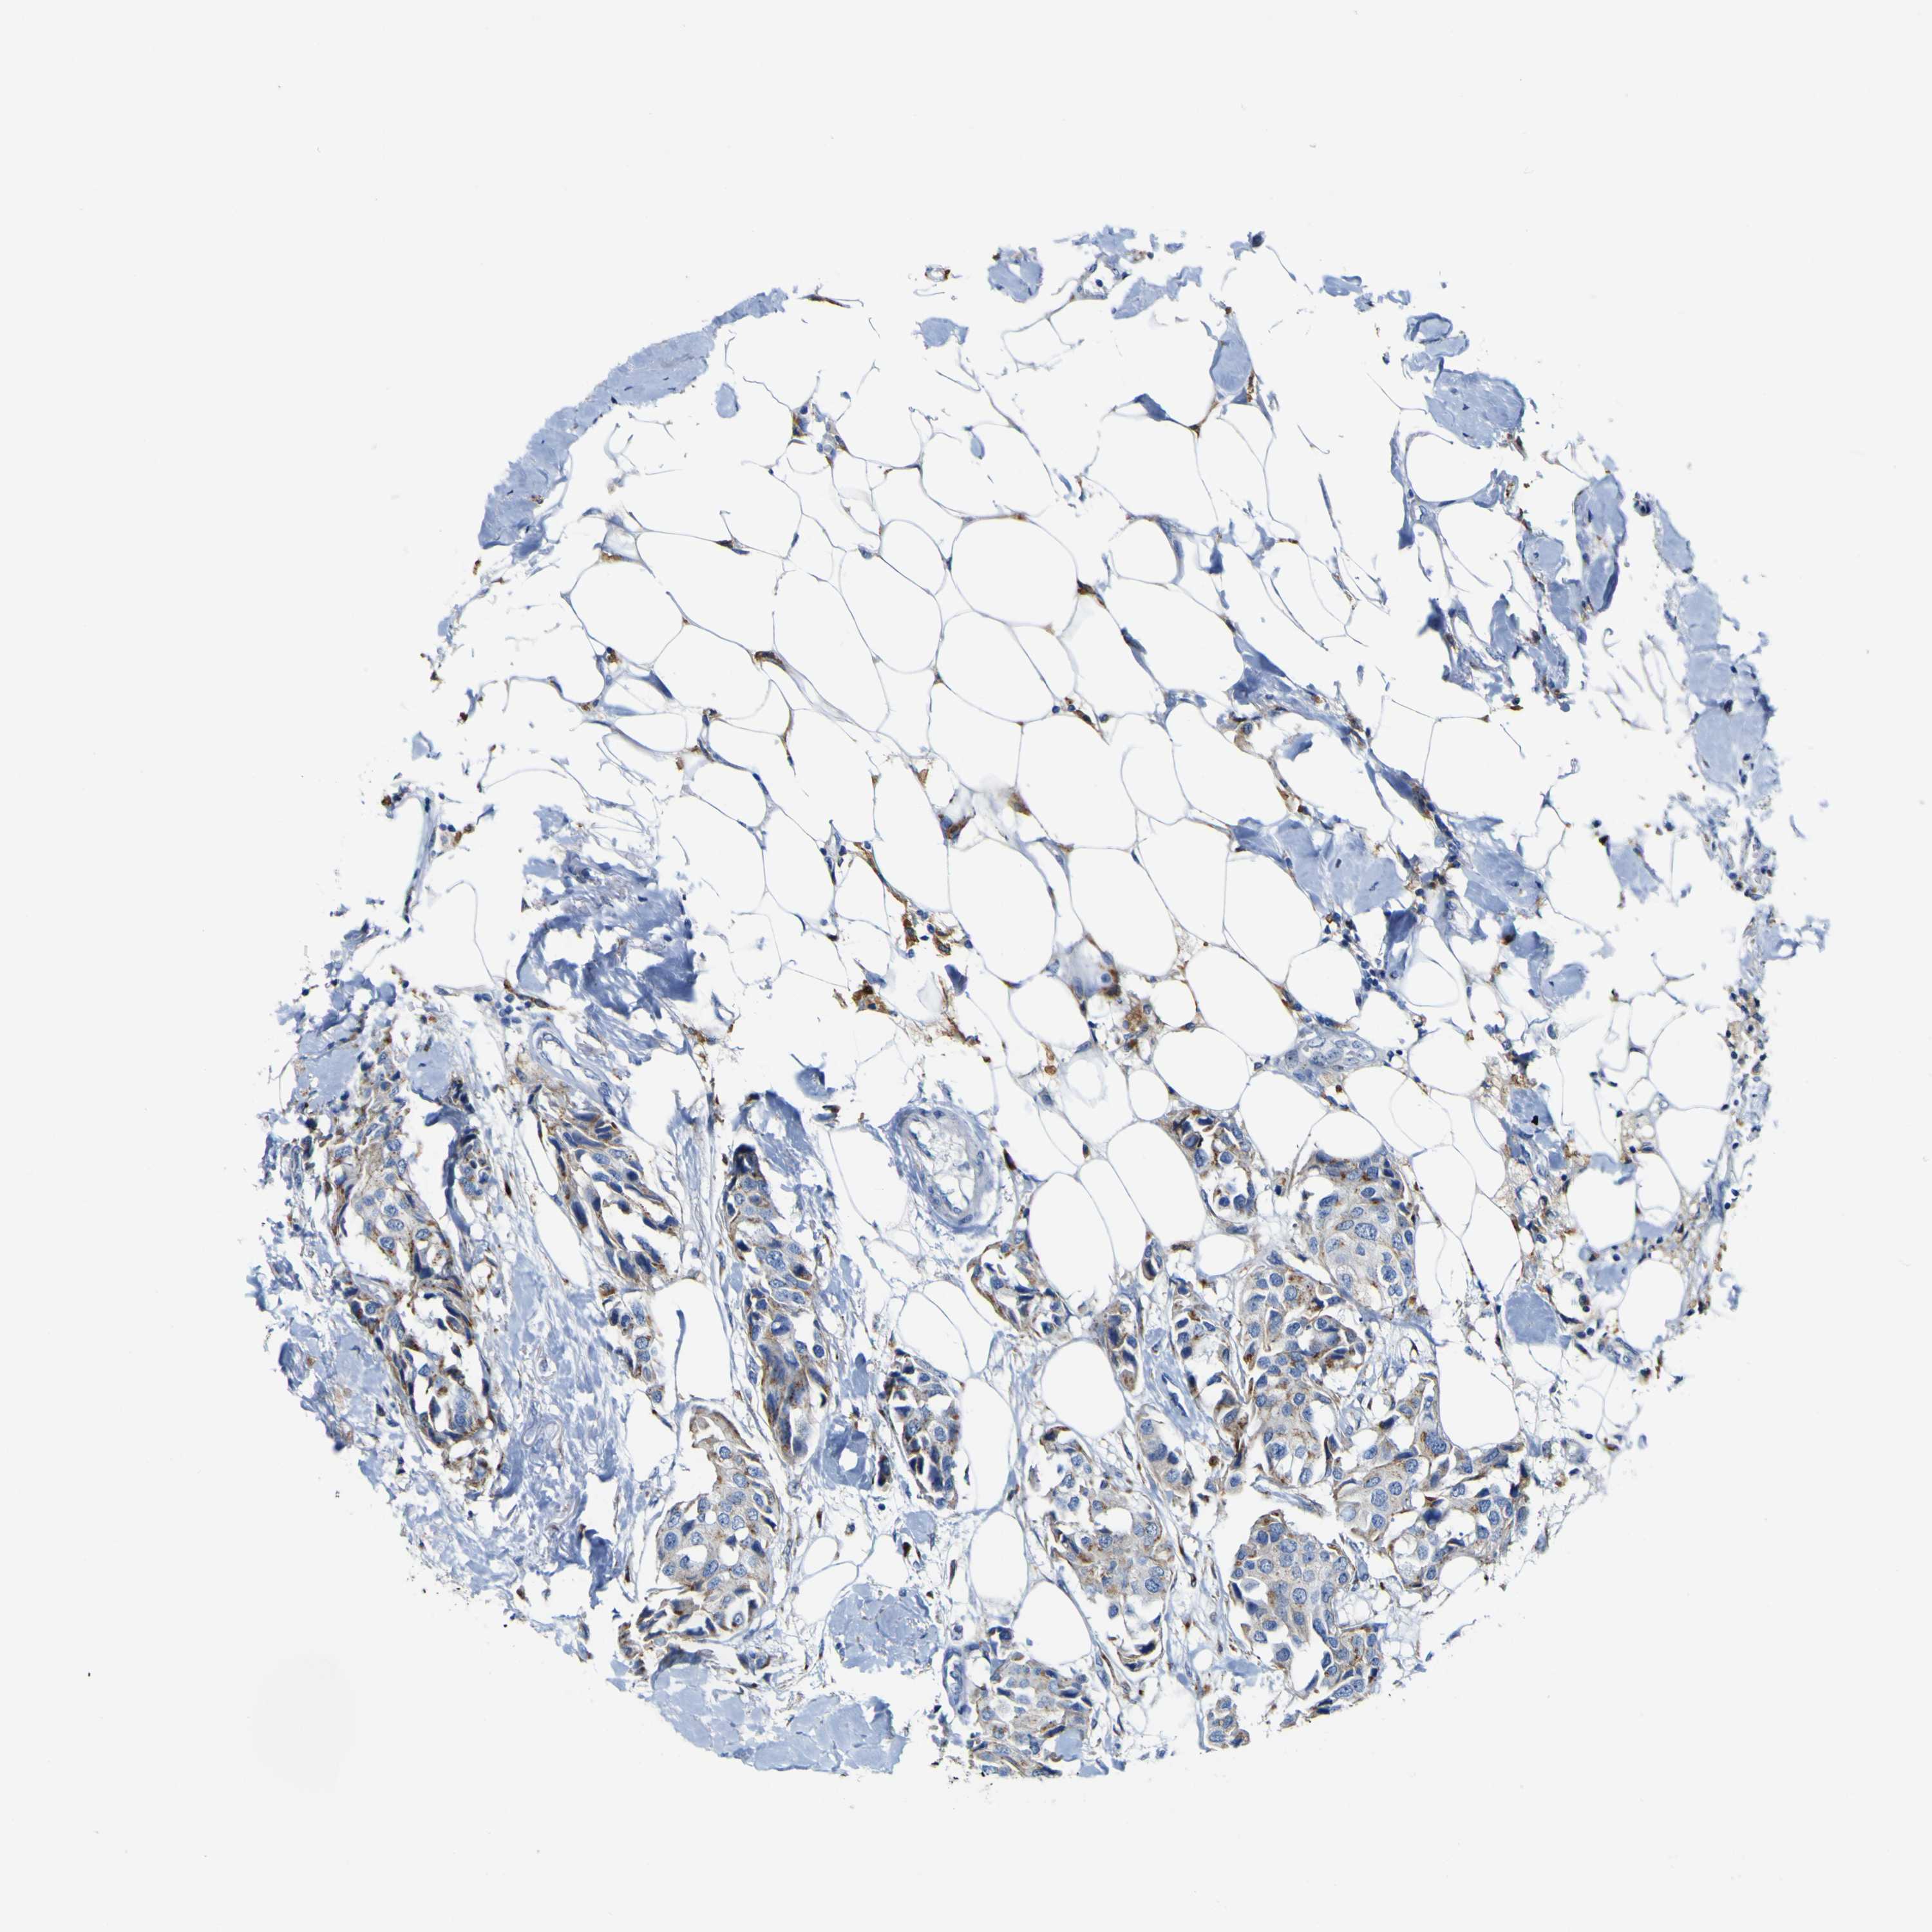

CANCER BREAST CANCER Show tissue menu

BRCA TCGA BRCA VALIDATION PROTEIN EXPRESSION